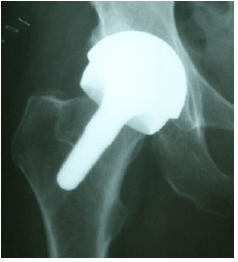

Ceramic-on-metal BMHR

A Birmingham Mid Head Resection femoral component can be used with a ceramic head. Hip simulator testing showed that the wear from a CoM bearing is much lower than the wear from a standard metal-on-metal bearing The BMHR stem was originally developed for use in patients with poor quality bone in the femoral head. These patients with severe cystic change in the femoral head or with osteonecrosis (dead bone in the femoral head) are not ideal candidates for hip resurfacing.

In patients with metal allergy the BMHR stem is proving to be very useful because it allows the use of a ceramic ball which against the same metal cup as a BHR.

The x-ray to the right shows a BMHR fitted with a ceramic head.

Laboratory testing of the ceramic on metal (CoM) bearings in a hip simulator has shown that the wear is phenomenally lower than the wear from a regular BHR.

Eighteen patients have so far received the CoM BMHR and in every case it was because the patient was not suitable for a metal-on-metal bearing. The metal ion release in these patients confirms the hip simulator finding and their urine and blood levels of cobalt are considerably lower than the levels seen in patients with BHRs.